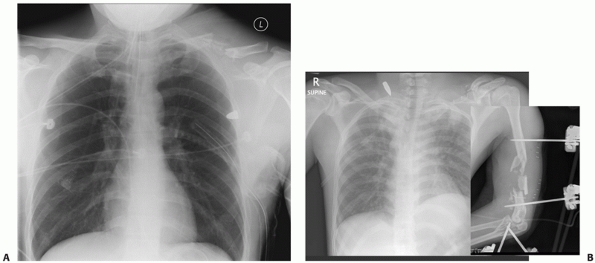

vehicular trauma are more likely to have associated injures to the

hemothoraces/pneumothoraces28,89,162 (Fig. 36-6).

![]()  |

FIGURE 36-6

Anteroposterior radiograph of the clavicle in a 42-year-old man involved in a motor-vehicle collision. Associated injuries include multiple ipsilateral upper rib fractures, an ipsilateral pneumothorax (arrows outlining collapsed lung), and multiple lower extremity fractures. This patient has four relative indications for operative fixation: (i) the severe displacement of the clavicle fracture, (ii) the multiple upper rib fractures, which tend to destabilize the shoulder girdle, (iii) the associated lower extremity fractures and the resultant need for immediate upper extremity use, and (iv) the pneumothorax, which is indicative of the degree of trauma applied to the shoulder.  |